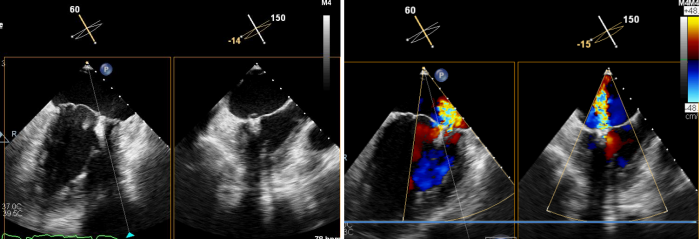

术前心脏彩超所示:二尖瓣返流

术前,超声科聂红军教授运用全数字化高端心脏彩色多普勒诊断仪,为患者进行食道三维超声综合评估,确定了二尖瓣返流量及返流分区。同时,在手术中实时监测二尖瓣瓣叶返流区与钳夹器的位置是否吻合,术后还可即刻探查二尖瓣返流量减少情况,如果把手术比作开车,那超声科就是手术的导航系统。

术中,蒋路平主任团队在经食道超声引导下通过股静脉穿刺房间隔将二尖瓣钳夹系统送入患者左心房到达二尖瓣口,然后医生全程在经食道超声引导下通过评估二尖瓣返流位置以及返流程度等精准夹合二尖瓣叶,整个过程都是在心脏不停跳的情况下完成。